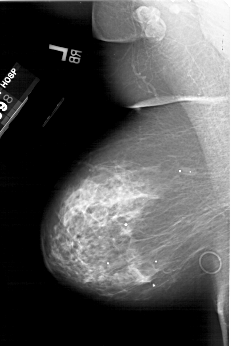

A_1987_1.LEFT_MLO

LEFT_MLO LINES 6226 PIXELS_PER_LINE 4156 BITS_PER_PIXEL 12 RESOLUTION 43.5 NON_OVERLAY

FILE: A_1987_1.RIGHT_MLO.OVERLAY

TOTAL_ABNORMALITIES 1

ABNORMALITY 1

LESION_TYPE MASS SHAPE IRREGULAR MARGINS ILL_DEFINED

ASSESSMENT 3

SUBTLETY 4

PATHOLOGY MALIGNANT

TOTAL_OUTLINES 1

BOUNDARY